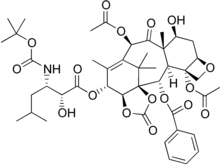

| Formula | C44H57NO17 |

| Molar mass | 871.930 g·mol−1 |